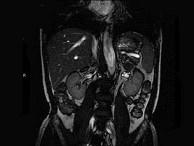

问题 男,52岁,下肢无力伴多饮多尿2年余,实验室检查:低血钾,血醛固酮水平及24小时尿醛固酮定量超过正常值,MRI检查如图所示,应诊断为()

选项 A.左肾上腺囊肿 B.左肾上腺腺瘤 C.左肾上腺嗜铬细胞瘤 D.左肾上腺髓脂瘤 E.左肾上腺转移瘤

答案 B